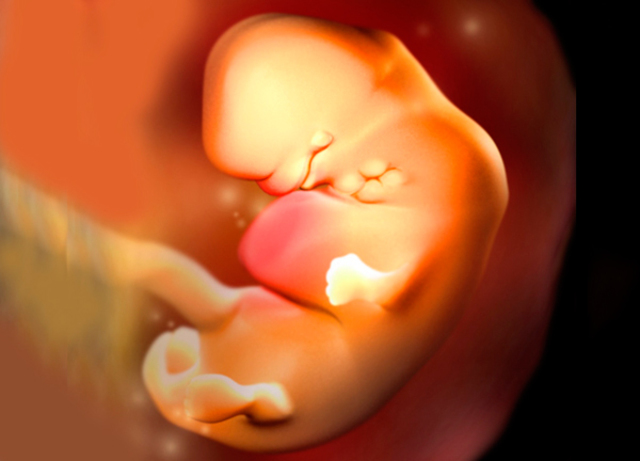

• Semana 9

Semana 9

Aparecen las manos con los dedos.

Las piernas se alargan, aparecen los pies con sus dedos correspondientes.

La cabeza sigue siendo la parte más grande en proporción con el resto del cuerpo.

En la cara, lo párpados cubren parcialmente los ojos. Los pabellones auriculares están bien formados. La boca se aprecia e incluso se abre.

Se observa una protuberancia común denominada tubérculo genital, que dará lugar más adelante a los genitales femeninos o masculinos.